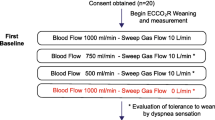

Data were collected prospectively. After several hours in stable condition on a preset NAVA level, blood gas analysis and ventilatory parameters were documented at five consecutive times, each data set for a period of 30 min: at baseline, after reduction of ECMO sweep gas flow to 50%, again after temporarily pausing sweep gas flow, after increase of FiO2 to achieve a saturation at or above 95% and finally again at baseline settings. Further information is given in the “Electronic supplementary material”.

PaO2, PaCO2 and pH

Oxygen transfer of the ECMO, calculated by multiplying the difference in oxygen content before and after the oxygenator by the blood flow, averaged 112 ± 37 ml/min. ECMO blood flow before and during measurements was 1.9 ± 0.36 l/min. At baseline all patients were in a stable state of oxygenation. Reducing sweep gas flow of the ECMO to 50% at unchanged blood flow resulted in most patients in an increase of PaO2 (Fig. 1). At a sweep gas flow of 0 l/min, which implies that extracorporeal gas transfer is stopped temporarily, all patients had an expected decrease of PaO2, which was controlled by the consecutive increase of FiO2 (Fig. 1; p < 0.05).

The estimated carbon dioxide elimination capacity of the ECMO was calculated with 161 ± 30 ml/min. Decreasing and turning off the sweep gas flow was compensated at least partially by all patients but one. Stable PaCO2 and pH values were observed because of ventilatory compensation (see below). Patient E with end-stage cystic fibrosis could not sufficiently increase pulmonary carbon dioxide elimination (Fig. 1) mainly caused by a low compliance of the respiratory system (11 ml/cmH2O). Consecutively, pH in this patient dropped considerably, whereas control within the physiologic range was maintained in the other patients (Fig. 2). Returning to baseline by turning on the sweep gas flow again was followed in most cases by a drop of PaCO2 and an increase of pH.

Stepwise reducing and turning off the ECMO sweep gas flow led in all cases to an increased electrical diaphragmatic activity (EAdi peak). Values ranged in mean from 2 to 32 μV with active sweep gas flow and from 4 to 47 μV with inactivated gas flow (Fig. 3). Proportional to the EAdi peak signal, peak inspiratory pressure (PIP) ranged in mean from 19 to 29 cmH2O with active ECMO and from 21 to 45 cmH2O with inactivated ECMO (p < 0.05, Fig. S1). With a preset PEEP level of 10 cmH2O or more, most patients did not increase the mean PIP above 30 cmH2O. Only patient E tolerated a PIP of more than 40 cmH2O with a very high EAdi peak signal in the futile attempt to control hypercapnia.

Tidal volume (V T) and minute ventilation (V E)

Since pressure is applied proportionally to the electrical activity of the diaphragm, in the NAVA mode tidal volumes vary from breath to breath, controlled by the patient’s respiratory centre. Tidal volumes with running ECMO ranged between 2 and 5 ml/kg predicted body weight. Reducing and turning off the sweep gas flow led in all cases to an increased V T (p < 0.01, Fig. 4), in patients A, D and F to a V T above 6 ml/kg. Hyperoxygenation by increasing the FiO2 with inactive ECMO did not reduce V T (p > 0.05, Fig. 4).

Minute ventilation (V E) increased rapidly in all patients after reducing and turning off the sweep gas flow (p < 0.05, Fig. S2). Ventilation increased 2.3-fold in patient 1, 1.3-fold in patient 2, 3.4-fold in patient 3, 2.3-fold in patient 4, 1.6-fold in patient 5 and 1.1-fold in patient 6 at turned off gas flow compared to baseline (Fig. S2). The rise in V E was partly a result of increased V T, but mainly caused by an increase in breathing frequency (Fig. S3).